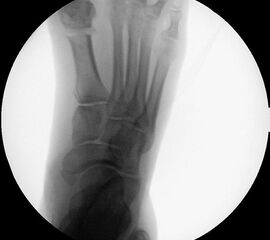

Präoperatives Röntgenbild Fuß d.p. mit eingezeichneten Winkeln. A) Intermetatarsalwinkel, B) Hallux valgus Winkel, C) Interphalangeal-Winkel.

Abbildung 2

• Operationsplanung anhand der Röntgenaufnahmen unter Beachtung wichtiger radiologischer Landmarks wie Intermetatarsalwinkel, Hallux valgus – Winkel, distaler Gelenkflächenwinkel (Distal Metatarsal Articular Angulation - DMAA), Metatarsaleindex und Sesambeinposition (Abb. 2).